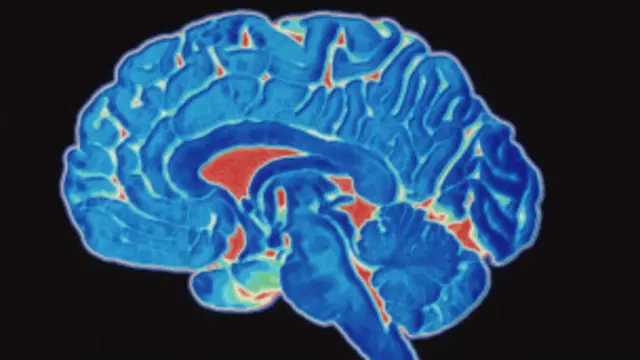

El cerebro humano, esa masa de un kilo y medio que llevamos en la cabeza, es la entidad más compleja que se conoce en el Universo.

Fuente de la imagen, Science Photo Library

"Las imágenes funcionales nos han demostrado que hay muy pocas regiones del cerebro que no se activan con algún estímulo", dice la profesora Sophie Scott del Instituto de Ciencia Cognitiva de la Universidad de Londres.

Un escáner funcional cerebral revela que un enorme número de neuronas entran en acción cuando planean e inician la contracción de los músculos de nuestros dedos y palma de la mano.